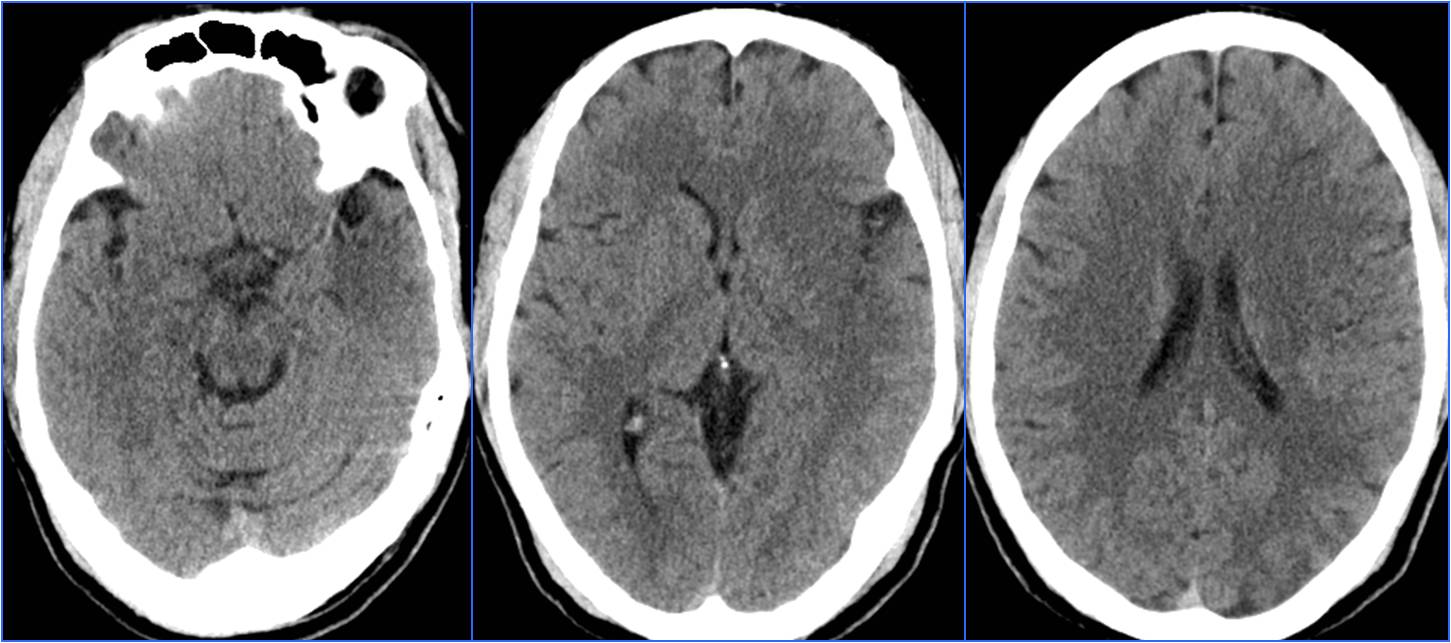

▼术前CT

▼术前MRA

▼术后24h头CT

▼术后72h 病情恶化,脑疝形成

▼去骨瓣减压,死亡

Case5 术后过度灌注、出血转化

》47岁,男,既往吸烟史20年

》12:00末次正常,15:00被发现言语不清、右侧肢体无力

》18:30到达急诊科,NIHSS 14分

》21:48结束手术

》术后24h NIHSS 8分